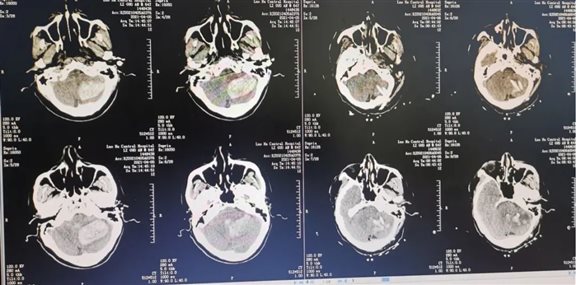

患者李某,因突发头痛头晕伴频繁呕吐3小时入院。入院时查体:神志模糊,双侧瞳孔等大等圆,直径约3mm,对光反射迟钝。言语不能,被动体位,四肢肌力检查不合作。颅脑CT检查示:左侧小脑脑出血,出血破入脑室,脑干受压,环池部分消失。

神经外科一病区、急诊科、监护室、手术室医疗团队立即为患者完善入院相关检查及检验,以最短时间完成术前准备,制定手术方案及备选方案,行3D打印辅助改良立体定向微创穿刺手术。复查可见引流管位置精确在位,小脑出血几乎引流干净,四脑室、中脑导水管复通。

术前小脑出血大于30ml、脑干受压、脑室梗阻,术后8小时出血基本引流完全,脑干受压、脑室梗阻解除。